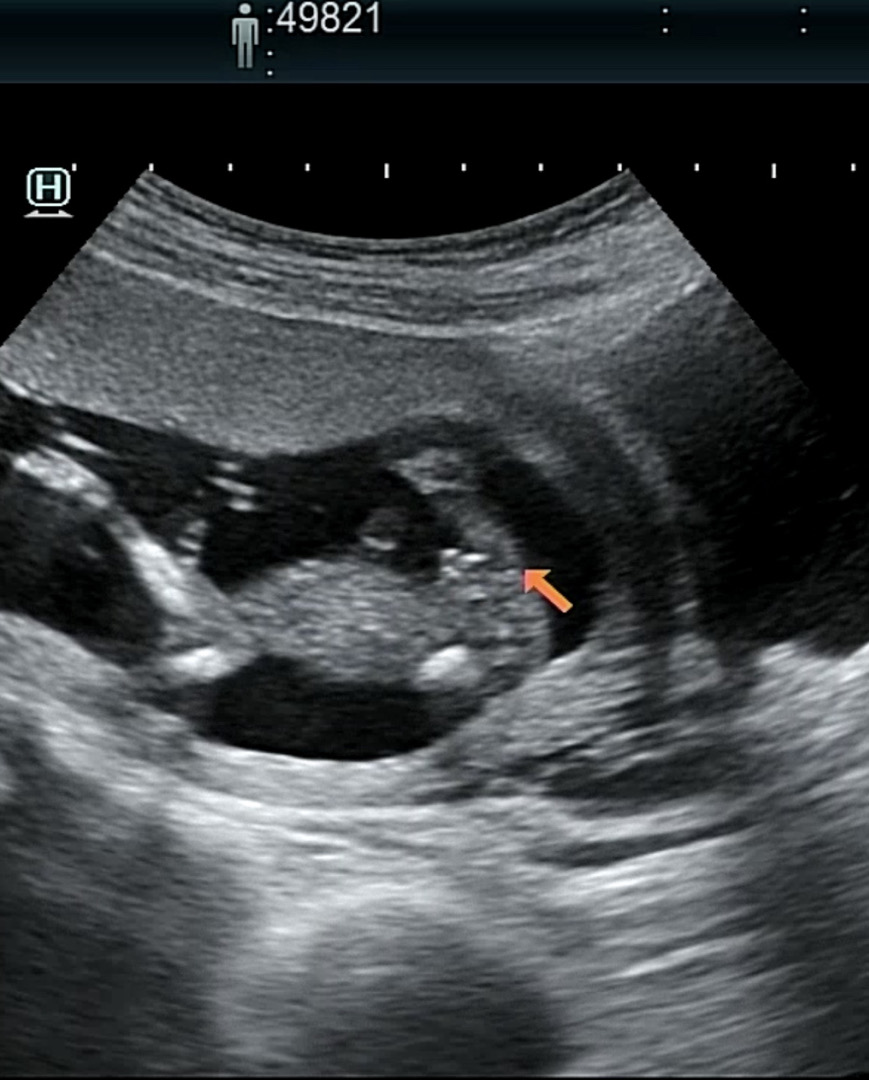

이건 13주 꼬츄...

2차 기형아 검사도 완료! 초음파 보자마자 다리 사이부터 찾는 슨생님... ㅋㅋㅋ 꼬츄... 라고 소근소근 말씀하시더라구요 휴~ 아무튼 이제 슬슬 친구들한테 말하려 하는데 다들 어떻게 말하셨나요???